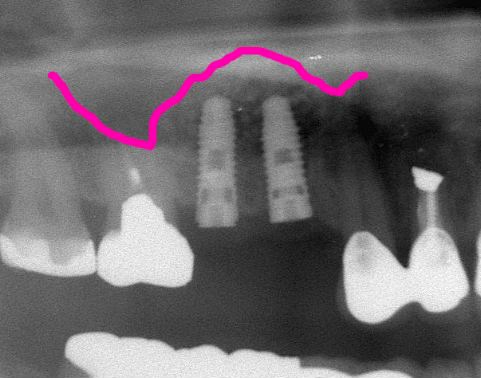

術前レントゲン